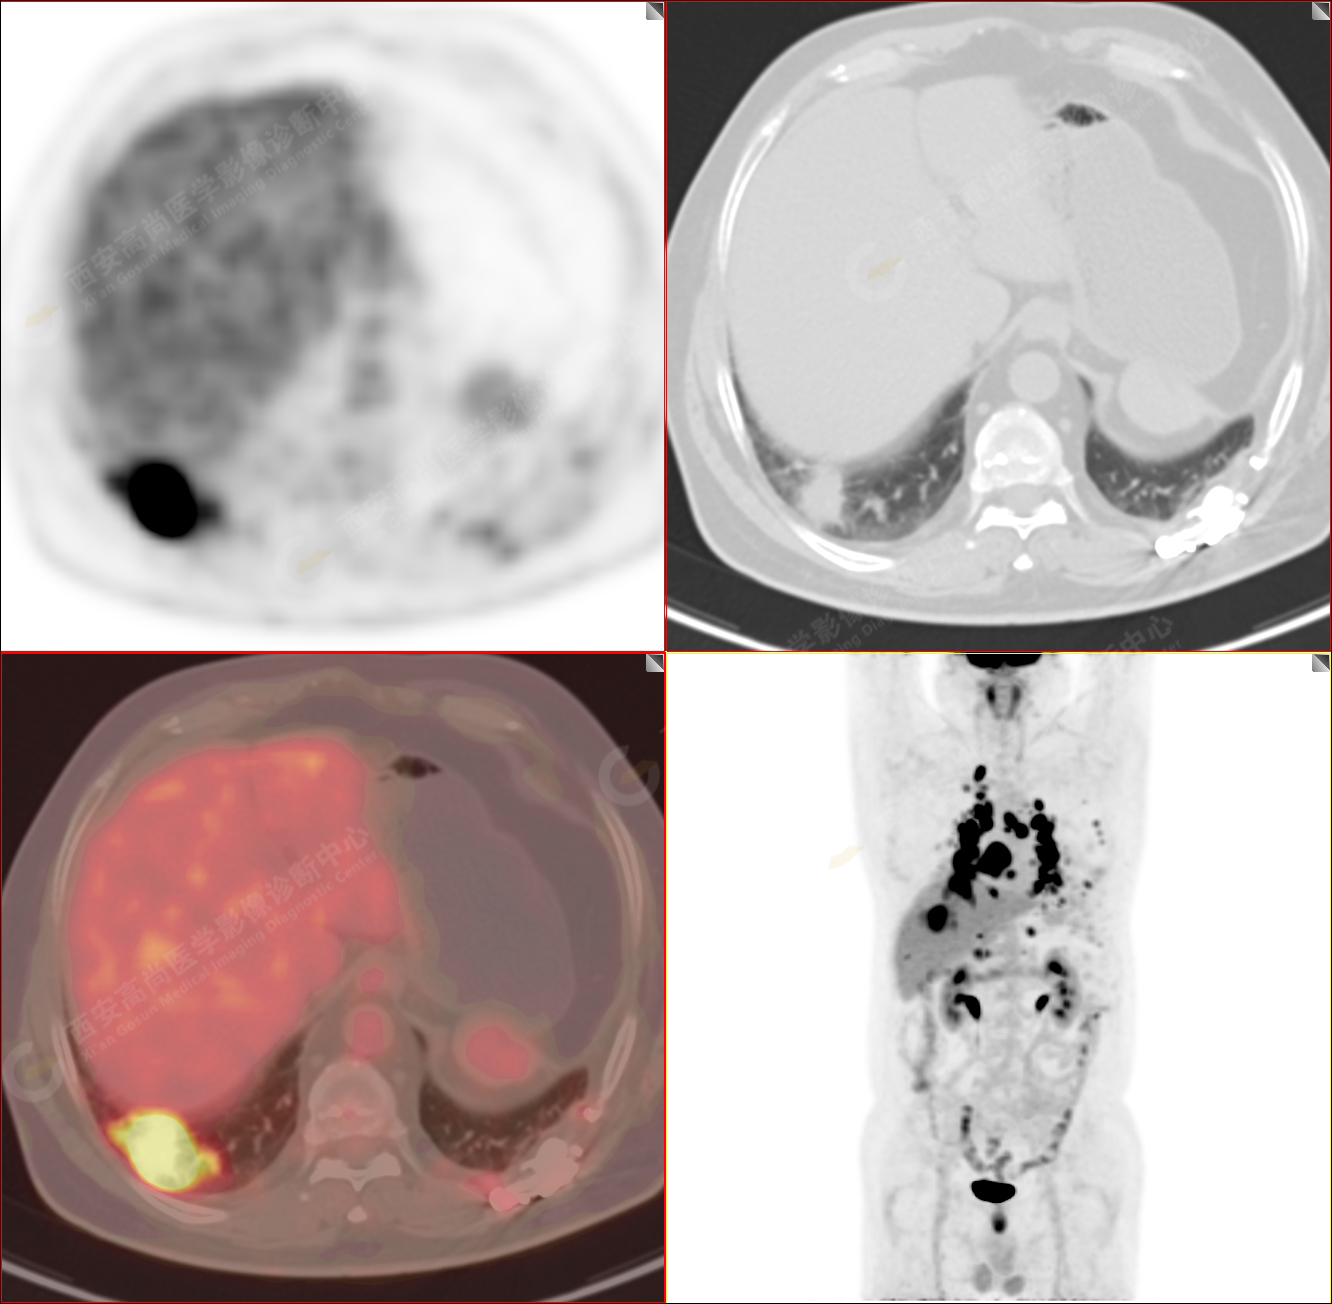

男性,53歲,頭暈半月入院,CT發(fā)現(xiàn)肺內(nèi)腫塊,雙肺多發(fā)大小不等實(shí)性及粟粒樣結(jié)節(jié),雙肺門(mén)及縱隔多發(fā)腫大淋巴結(jié)。病程中無(wú)發(fā)熱、胸悶氣及胸部不適。既往:左側(cè)肋骨外傷史。

PET/CT圖像